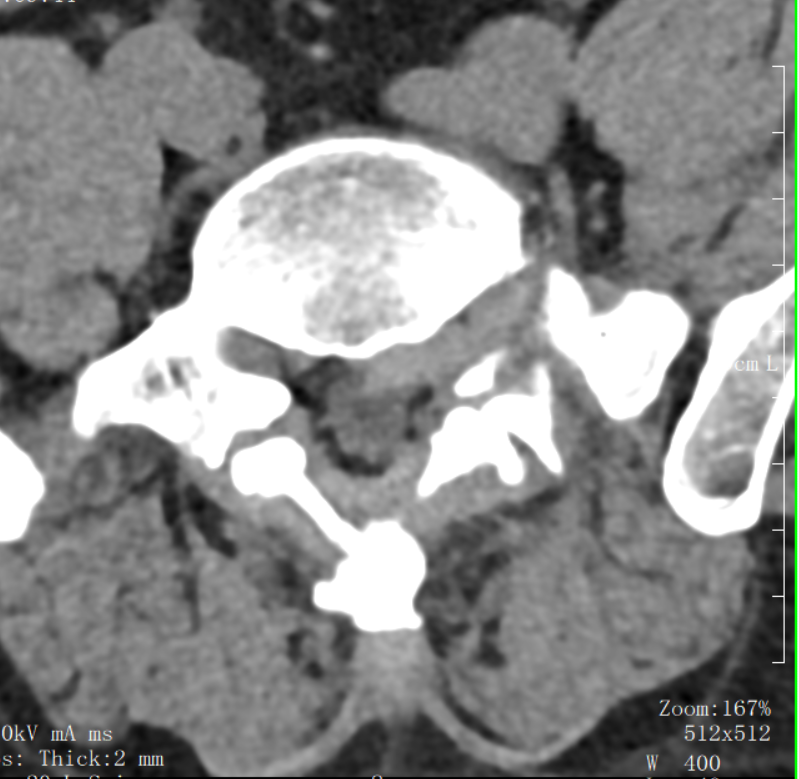

▲術前CT檢查

據悉,患者年逾七旬,因長期腰腿疼痛、麻木困擾,行走困難,生活質量急劇下降。入院后,經詳細檢查,被確診為“腰椎滑脫伴椎間盤突出”。這是一種常見的脊柱退行性疾病,對于高齡患者而言,傳統的開放手術創傷大、出血多、恢復慢,手術風險相對較高,讓許多老人望而卻步。